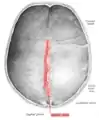

The sagittal suture, also known as the interparietal suture and the sutura interparietalis, is a dense, fibrous connective tissue joint between the two parietal bones of the skull. The term is derived from the Latin word sagitta, meaning arrow.

The sagittal suture is formed from the fibrous connective tissue joint between the two parietal bones of the skull.[1] It has a varied and irregular shape which arises during development.[1] The pattern is different between the inside and the outside.[1]

Two anatomical landmarks are found on the sagittal suture: the bregma, and the vertex of the skull. The bregma is formed by the intersection of the sagittal and coronal sutures. The vertex is the highest point on the skull and is often near the midpoint of the sagittal suture.